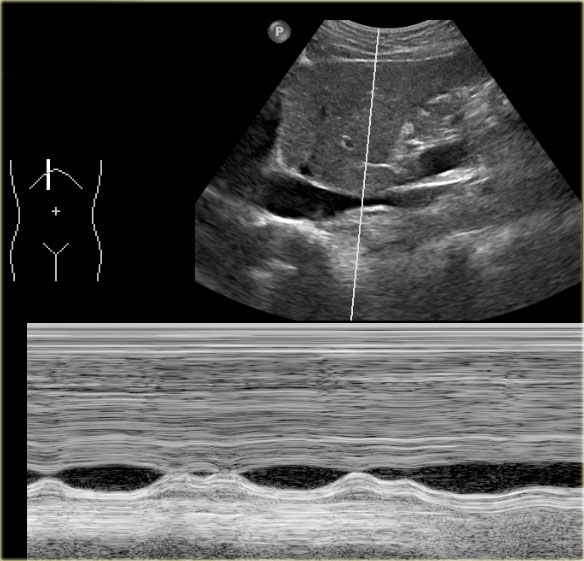

Dilatation of IVC and hepatic veins on US images in a patient with RV failure Dilatation of IVC and hepatic veins on US images in a patient with RV failure

Sonographic signs of RV failure:

• Dilatation of the inferior vena cava (IVC) and hepatic veins

• Hepatomegaly

• Ascites

The indication for ultrasound examination in many of these patients is abnormal liver function tests.

It is therefore important to consider the possibility of RV failure when a patient presents with liver enzyme abnormalities.

Under normal conditions dynamic ultrasound will demonstrate changes in caliber of the IVC.

These changes in caliber can be attributed to variations in blood flow in the IVC in accordance with the respiratory and cardiac cycles.